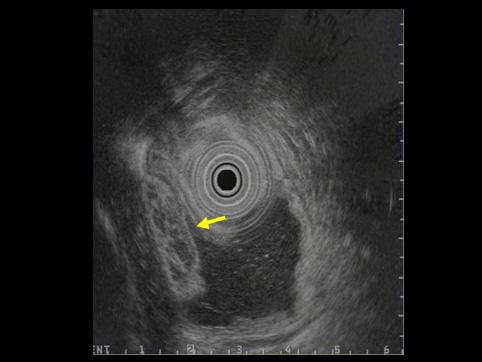

clasificación del pacienteTumor Maligno del Sistema Linfático/Linfoma Maligno

parte(separada por órganos)estómago(región)/cuerpo

método de exámenEcografía

clasificación ectoscópica de tumoresTipo 1(Tipo protuído)/

diámetro mayor del tumor35 - 40

grado de penetraciónmp